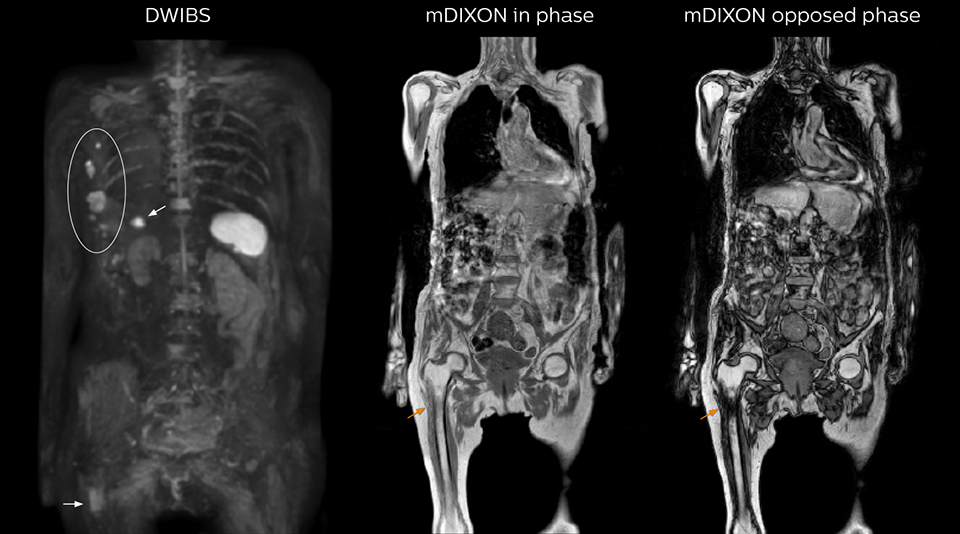

“The DWIBS sequence’s value in oncology cases is due to the high contrast it creates between lesions and surrounding tissue. Whole body DWI is requested by physicians who need to clarify TNM staging or determine therapeutic strategies, oncologists in need of diagnosis or follow-up scans, surgeons who need to see the presence of distant lesions that are sometimes difficult to detect by CT before surgery, and urologists for the evaluation of bone lesions, and the effect of chemotherapy and radiotherapy.”

After implementing the improved whole body protocol, the radiology team initially did not see a large increase in referrals, although Dr. Nobusawa saw clinical cases where the DWIBS images provided him valuable information for diagnosis. This is why Dr. Nobusawa and Mr. Naka started to actively educate referring physicians about the value of whole body DWIBS. They organized several presentations for physicians in the hospital, where they explained how DWIBS can be of value in oncology patients. The information it provides can be useful for physicians when staging cancer, as well as when determining or adjusting treatment strategy. Mr. Naka remembers some cases where DWIBS provided remarkable information. “In one example, DWIBS visualized bone lesions that could not be seen on PET or SPECT. In another case we had found a bone lesion when a normal L-spine scan for narrowing of the disk space was done. One extra DWIBS scan (2 stations, 8 minutes) demonstrated a lesion that later was confirmed to be the primary region of cancer.”